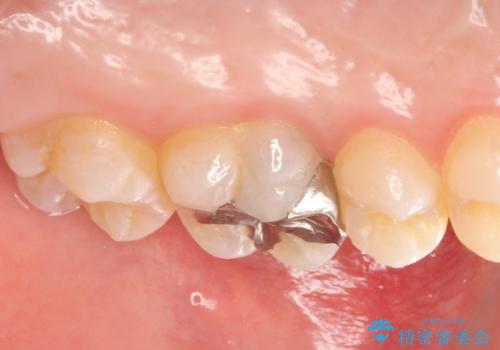

- 3日ほど前から何もしなくても左上奥歯がズキズキ痛むので診て欲しいといらっしゃった方の症例です。

検査の結果左上6に持続痛を認めたため根管治療を行い、症状の緩解を確認後オールセラミッククラウンによる補綴を行いました。